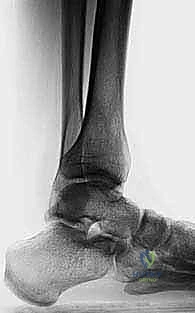

تشريح مفصل الكاحل وعظام الساق

لفهم أهمية هذه الجراحة، يجب أن نغوص في التشريح المعقد لمفصل الكاحل. يتكون مفصل الكاحل من التقاء ثلاثة عظام رئيسية:

1. عظمة الساق الكبرى (Tibia): وتحديداً الجزء السفلي منها الذي يرتكز عليه وزن الجسم بالكامل.

2. عظمة الشظية (Fibula): العظمة الجانبية الصغرى التي تساهم في استقرار المفصل.

3. عظمة الكاحل (Talus): العظمة التي تربط الساق بالقدم وتسمح بحركة الانثناء والانبساط.

عندما يكون المحور الميكانيكي للساق مستقيماً، يتوزع وزن الجسم بالتساوي على سطح الغضروف المفصلي لعظمة الكاحل. ولكن، في حال وجود تشوه زاوي (سواء تقوس للداخل Varus أو للخارج Valgus)، يتركز وزن الجسم بالكامل على مساحة صغيرة جداً من الغضروف. هذا الضغط الهائل والمستمر يؤدي إلى تآكل الغضروف بسرعة تفوق قدرة الجسم على تجديده، مما يمهد الطريق لخشونة الكاحل المبكرة.